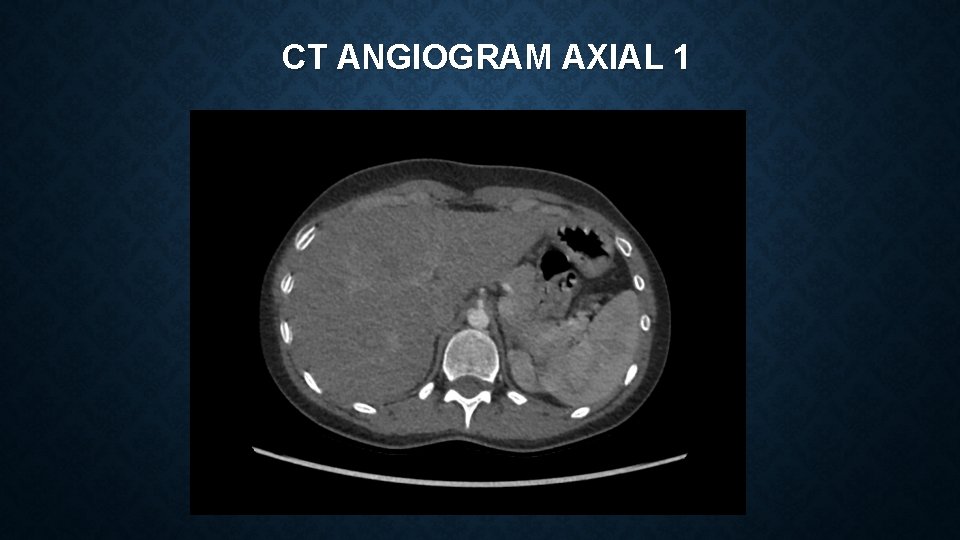

CT ANGIOGRAM AXIAL 1

MEDIAN ARCUATE LIGAMENT SYNDROME Vague constellation of symptoms which can include : • epigastric pain, postprandial pain, chronic non-specific abdominal pain, nausea, vomiting, weight loss Often a diagnosis of exclusion – reliant on clinical features and imaging findings Investigations include – CT angiogram and duplex ultrasonography CT – focal narrowing of coeliac artery with post-stenotic dilatation USS – Peak systolic velocities of >200 cm/s are suggestive of MALS